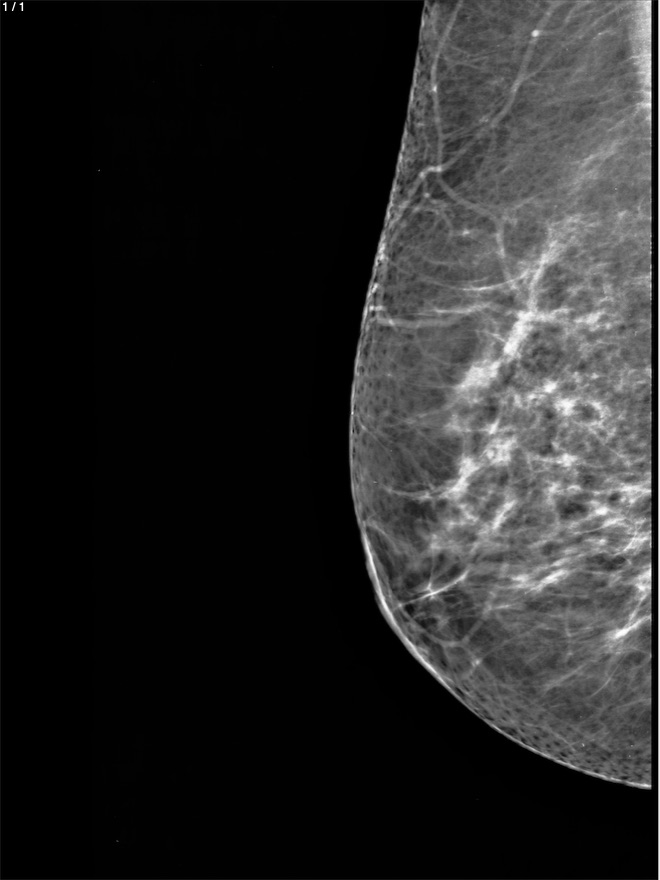

Blanca Elena Hidalgo Leon - Unnamed